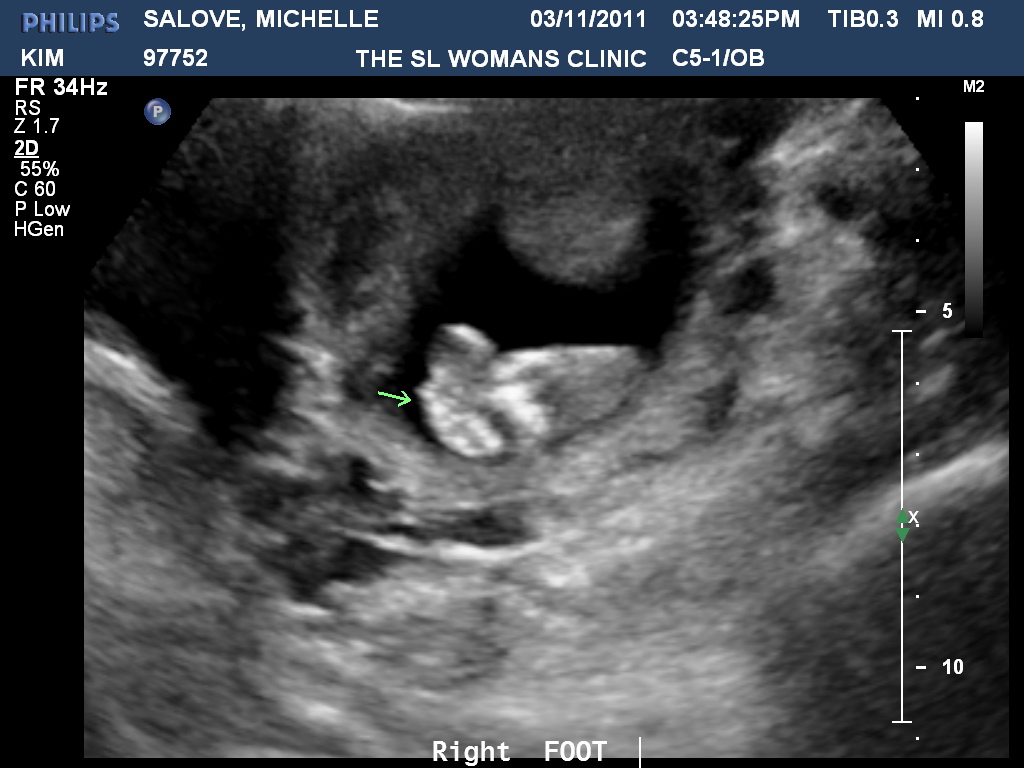

Sweet little piggies...